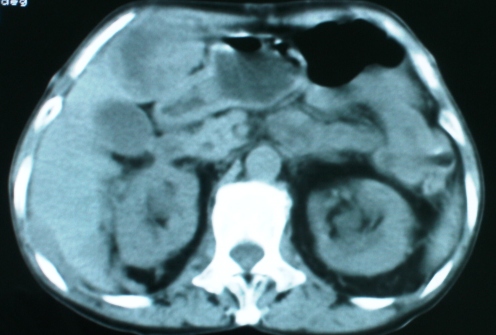

以下是引用zsl6918在2008-11-4 19:14:00的发言:[br]多发转移性改变,子宫改变不除外为原发灶